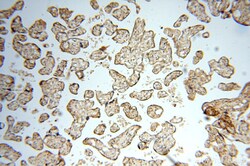

18351-1-AP IHC

Immunohistochemistry